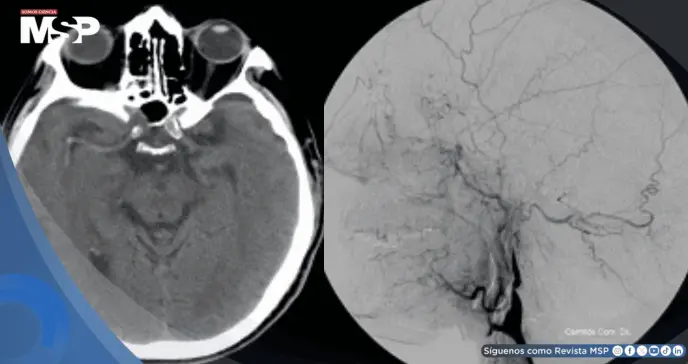

Las pruebas de imagen resultaron cruciales para confirmar las sospechas clínicas. La tomografía computarizada cerebral inicial mostró signos de obstrucción arterial, mientras la angiografía, un estudio especializado de los vasos sanguíneos, reveló el estrechamiento característico de la arteria carótida con la apariencia de "cola de rata" que confirmaba definitivamente la disección arterial.

Estudios complementarios como el ultrasonido carotidéo también mostraron la estrechez vascular, completando el panorama diagnóstico.